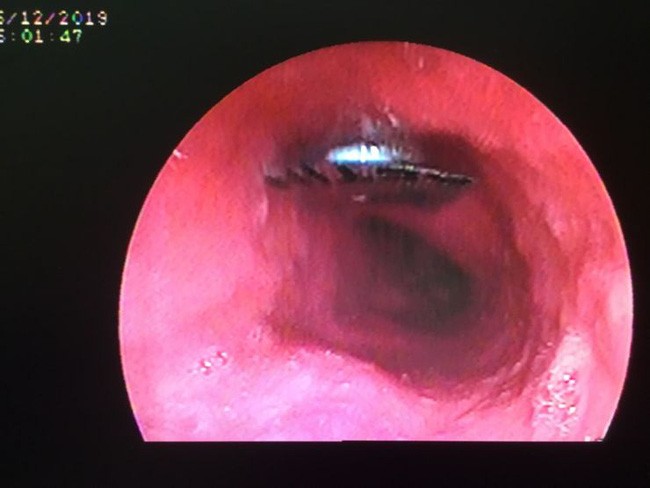

Theo bệnh viện Quận 11, ngày 26/12 bệnh viện đã tiến hành lấy dị vật vỏ thuốc thành công cho bệnh nhân nữ Đ.U.L. 41 tuổi vào viện trong tình trạng đau tức ngực sau xương ức do nuốt phải vỏ thuốc còn nguyên vỏ.

Theo đó, người phụ nữ 41 tuổi nhập viện trong tình trạng đau tức ngực sau xương ức. Sau đó, bệnh nhân được chuyển vào phòng Nội soi để tiến hành nội soi, chẩn đoán cho thấy dị vật viên thuốc còn nguyên vỏ kích thước 9 x 9mm, hình vuông cạnh sắc bén như dao ở thực quản đoạn giữa, có nguy cơ gây thủng thực quản vào trung thất có thể dẫn đến tử vong.

Để tránh nguy cơ viên thuốc sặc vào phổi, Đơn vị Nội soi mời bác sĩ Khoa Gây mê hồi sức tiến hành tiền mê để nội soi gắp dị vật an toàn cho bệnh nhân. Do dị vật sắc bén nên ê kíp bác sĩ phải dùng chụp dị vật bằng silicon để bao dị vật tránh chảy máu và thủng thực quản khi kéo dị vật ra ngoài.